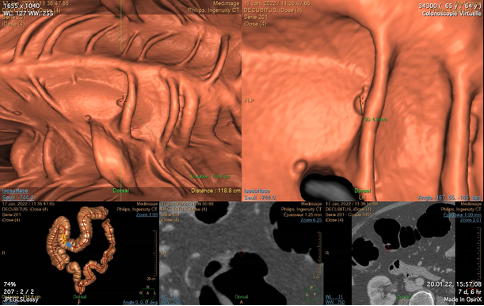

Cancer colorectal

Examens d’imagerie médicale

Colonoscopie virtuelle dans les cas où la coloscopie n’est pas possible (côlon trop long, obstrué ou coudé). Cet examen est moins invasif et bien toléré. Il permet la détection des polypes de petite taille et la visualisation des organes voisins.

Programme de dépistage cantonal

Recherche de sang occulte dans les selles tous les deux ans ou coloscopie tous les dix ans à partir de 50 ans.